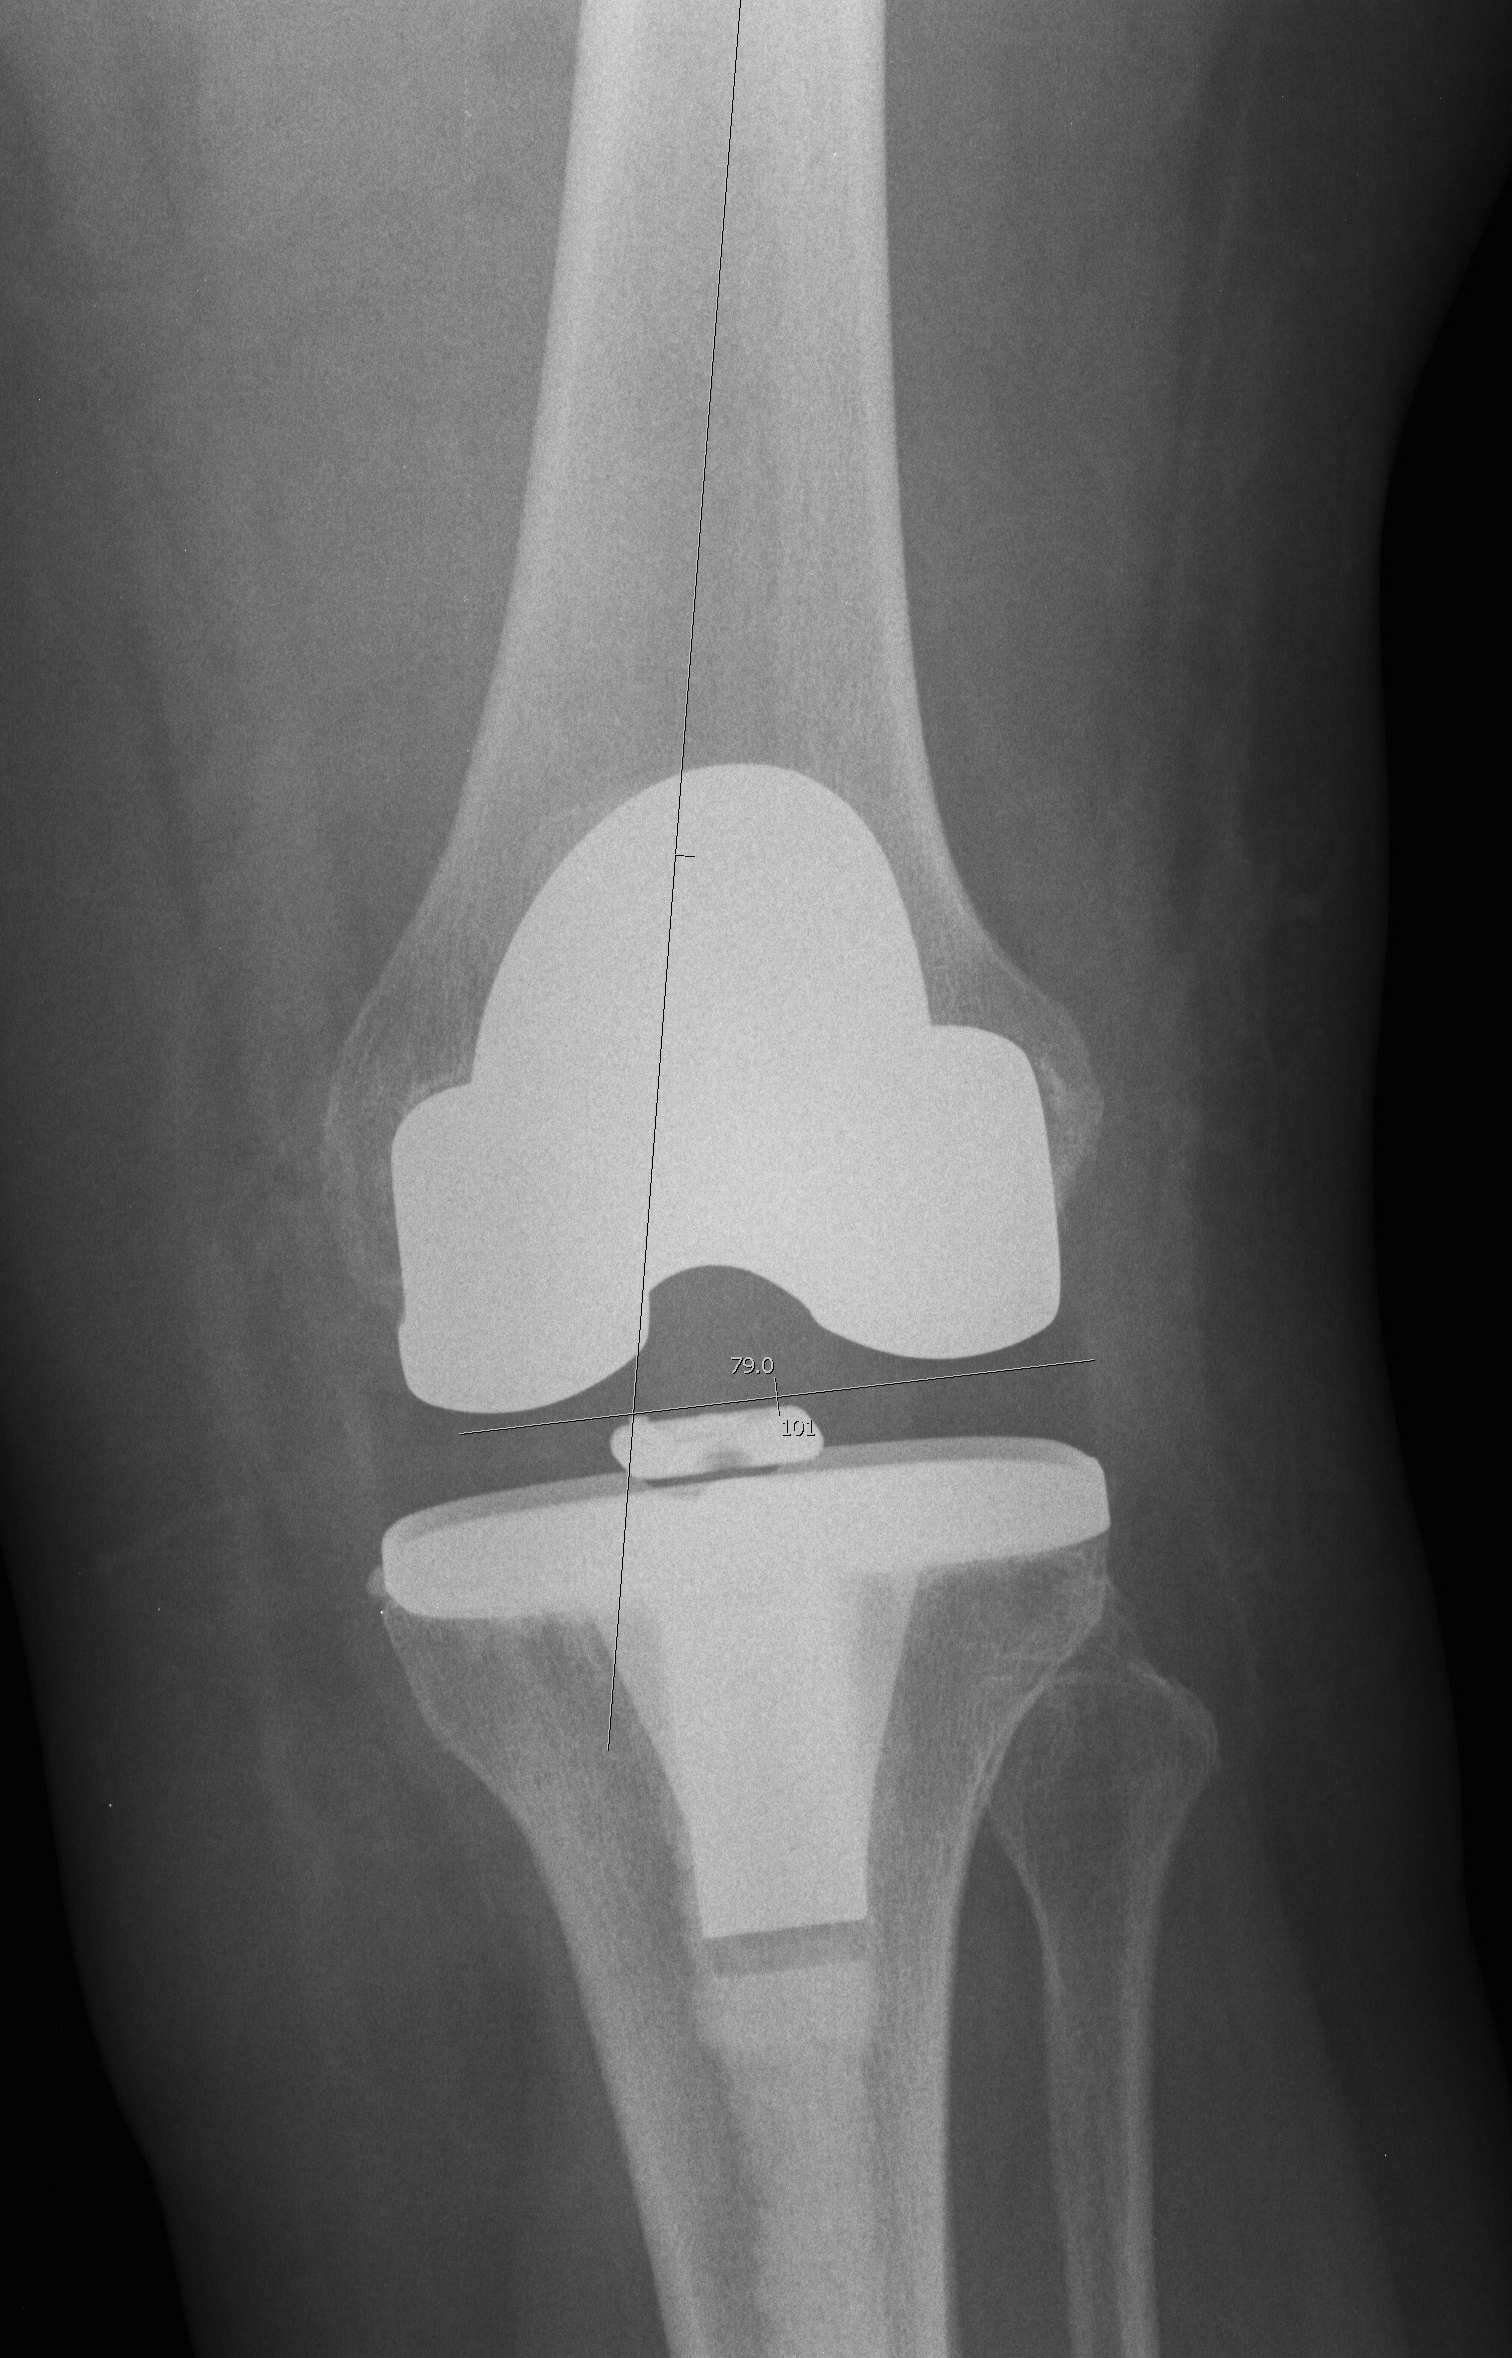

1. Reduces outliers

Will place 90% of TKR's within mechanical axis +/- 3o in coronal plane

- reduces outliers

- will take a long time to see if this improves implant survival

- require large numbers of patients in randomised trials followed over 15-20 years to see a significant result

Lutzner et al JBJS Br 2008

- RCT image less computer navigation

- reduced number of outliers in convential group

- CT analysis showed tibial rotation inaccurate

Spencer et al JBJS Br 2007

- RCT of navigated v conventional

- no difference in functional outcome at 2 years